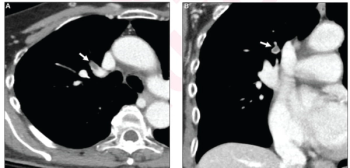

Artificial intelligence facilitated a 96.2 percent sensitivity rate for incidental pulmonary embolism (IPE) on contrast-enhanced CT chest or abdomen exams, according to new prospective research involving over 4,300 patients.